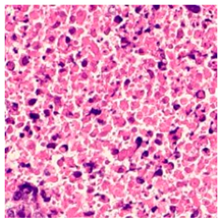

Related Work

2.4. Model Interpretability

3.6. Visualizing Interpretability in CRC Classification Using ADFMs

4. Discussion